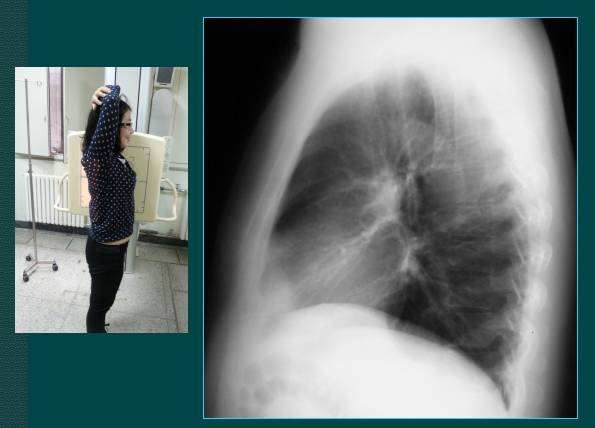

2.胸部侧位片

上图是胸部侧位片的拍摄,一般采取右侧位拍片,如果看心脏影可以采取左侧位片。

上图为胸部侧位片